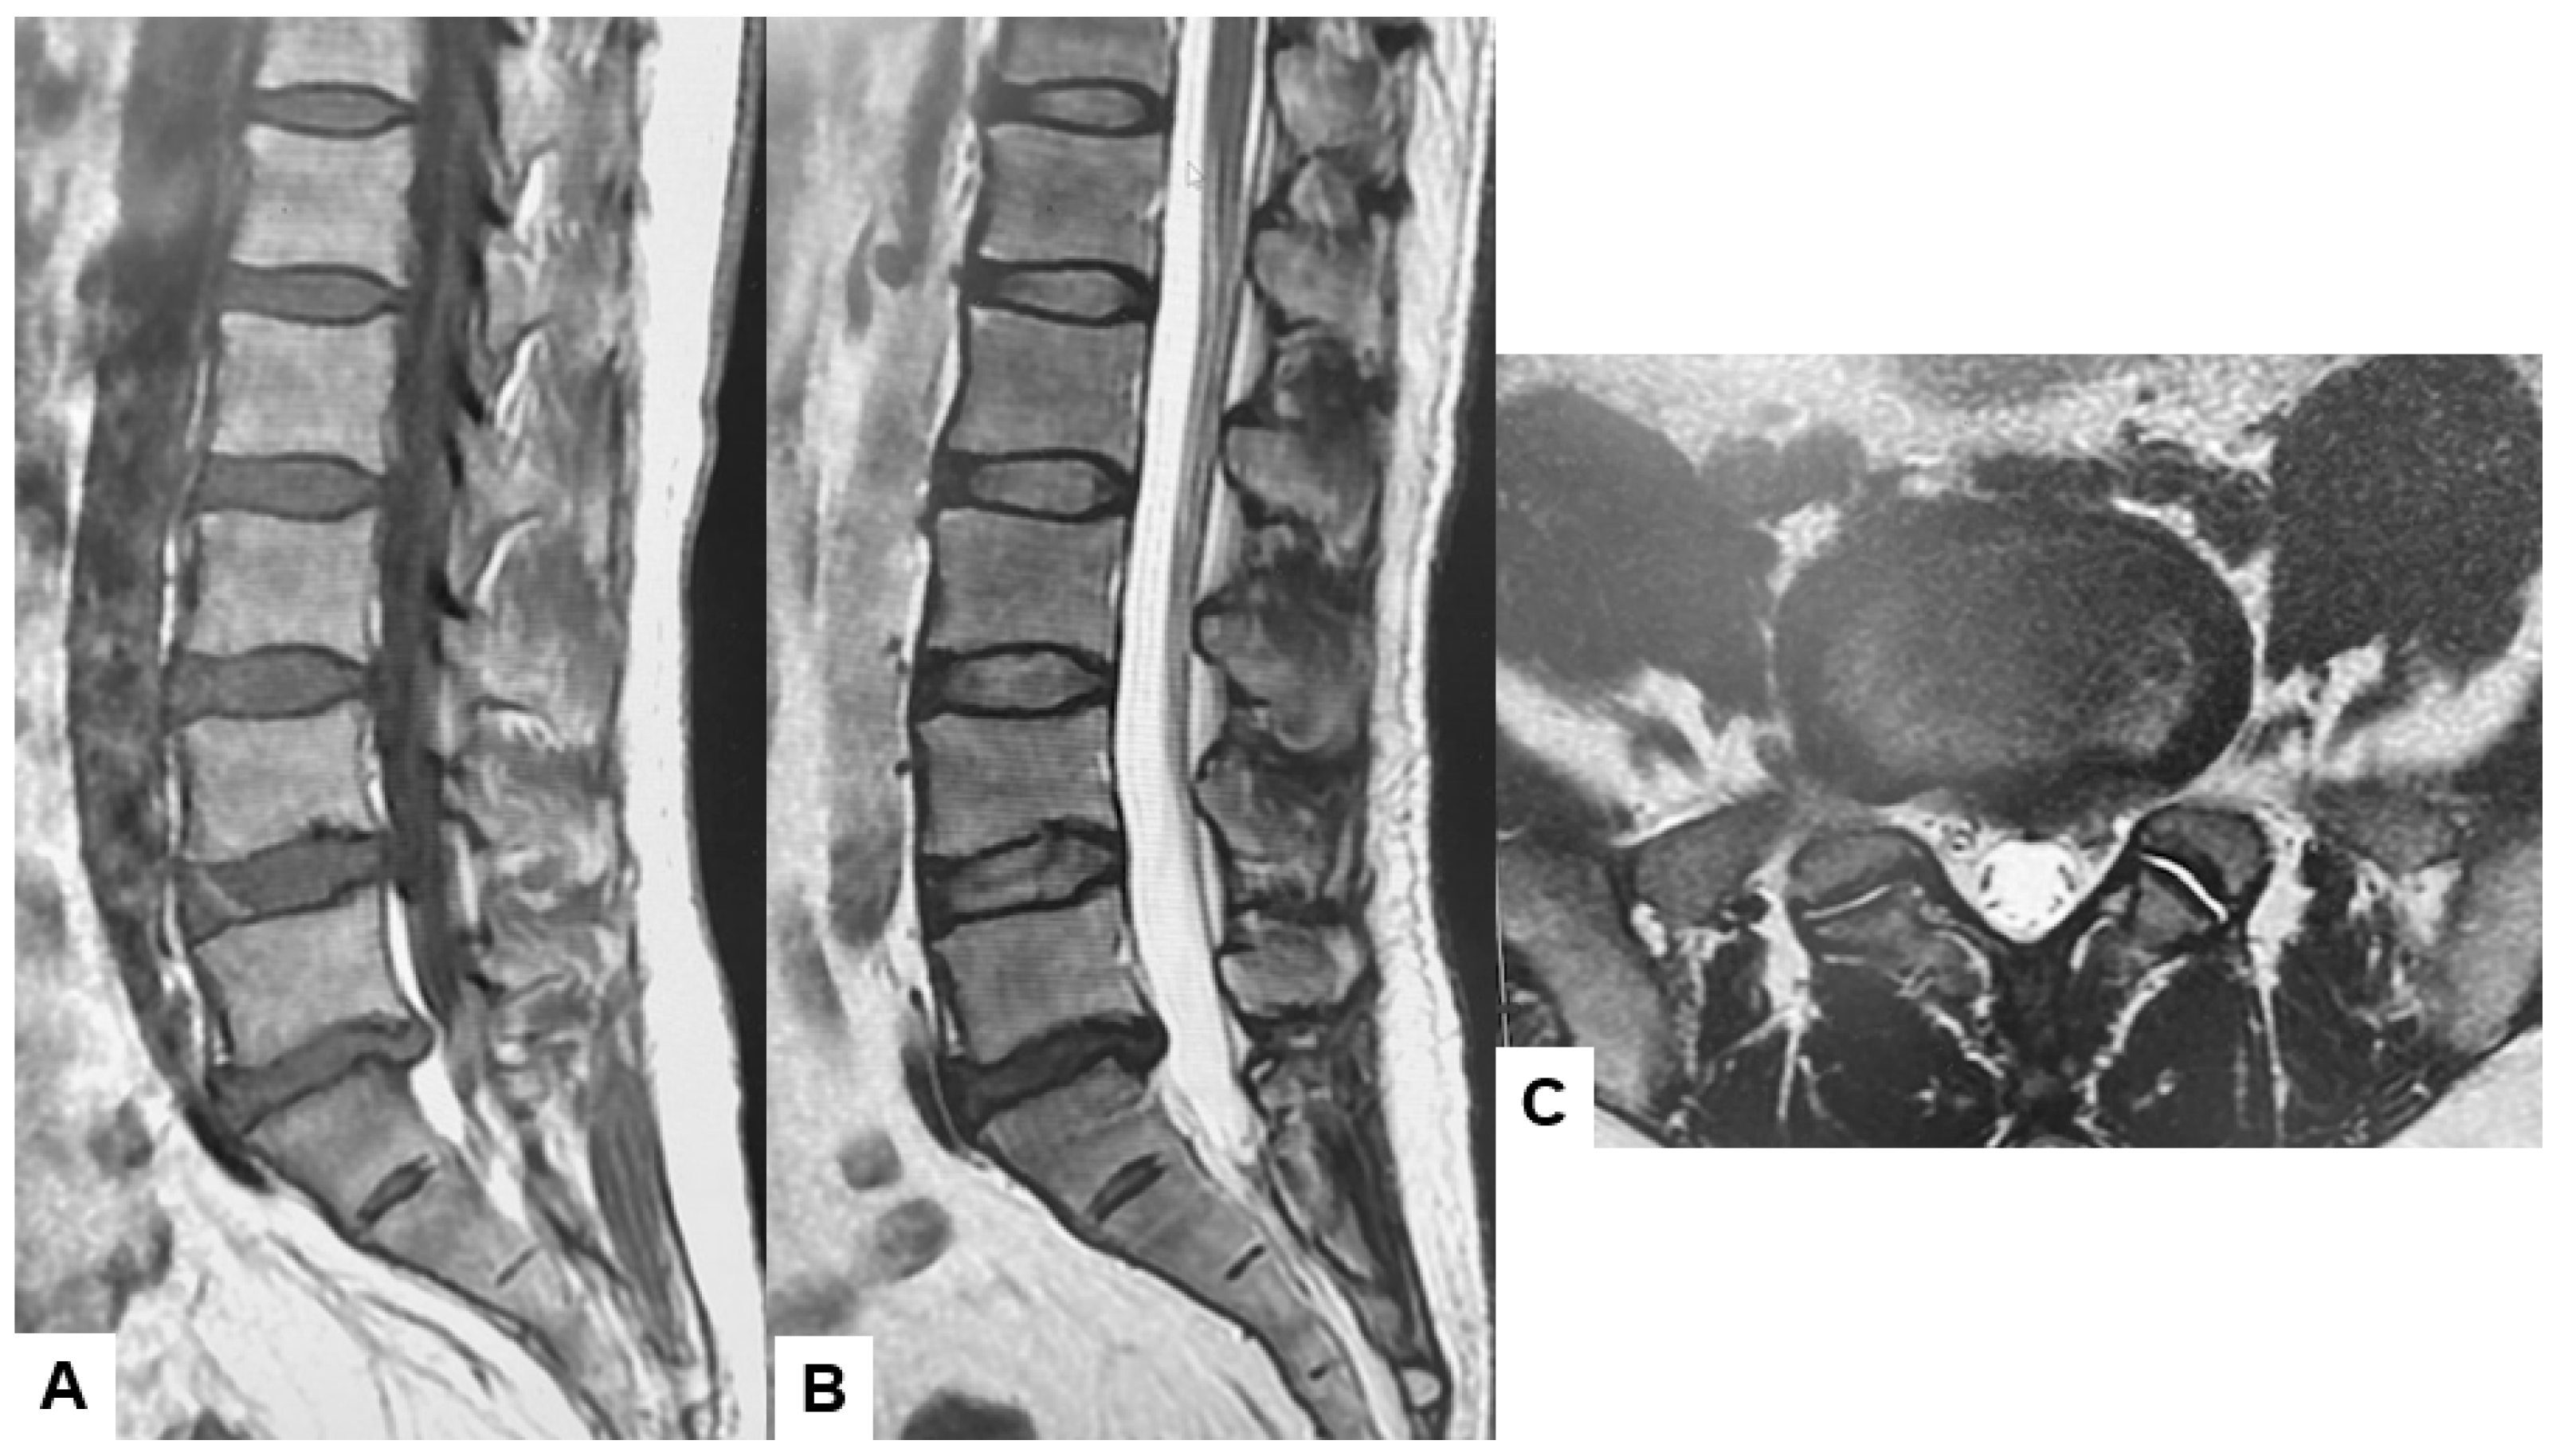

A major diagnostic shift occurred in the last quarter of the 20th century through the utilization of MRI [26]. This diagnostic tool revolutionized spine diagnostics by providing the high-resolution visualization of soft tissue structures, including the intervertebral disks, spinal cord, and nerves [27]. MRI utilizes the magnetic properties of protons within human tissue. When placed in a strong magnetic field, the radiofrequency pulse can align and manipulate these protons. Protons release energy captured as signals, which are then mathematically reconstructed by a computer to form detailed images. Body tissue composition, such as differences in water, fat, and protein content, contributes to the contrast seen in MRI sequences such as T1-weighted, T2-weighted, and STIR (Short Tau Inversion Recovery). This contrast allows spine surgeons to differentiate among intervertebral disks, muscles, ligaments, the spinal cord, and pathological lesions with remarkable clarity [28,29,30]. This capability is crucial for accurately diagnosing spinal pathologies. Therefore, MRI is the gold standard for spinal pathologies involving soft tissues (Figure 3).

The broad-spectrum clinical application of MRI includes degenerative spinal pathologies, spinal trauma, tumors, and infections. MRI provides superior imaging for ligamentous injuries such as ligament tears compared to CT. Moreover, spinal cord contusion, edema, and epidural hematoma can be detected in the early phases of spine trauma, which is crucial for ensuring positive spinal trauma outcomes [31,32,33]. Furthermore, contrast-enhanced MRI plays a significant role in diagnosing spinal tumors and infections, which is currently the first-line diagnostic tool [34,35,36,37].

The superior diagnostic capabilities and the ability to assist surgeons in performing meticulous preoperative planning make MRI a widely used diagnostic tool for spinal disorders [38,39,40].

Figure 3. Forty-two-year-old M, left L5/S lumbar disk herniation, (A) T1-weighted midsagittal image, (B) T2-weighted midsagittal image, (C) T2-weighted axial image at L5/S1. Lumbar disk herniation (median and paramedian) is indicated at left L5/S1.